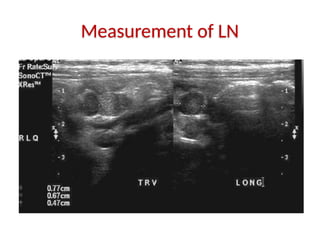

Measurement of LN